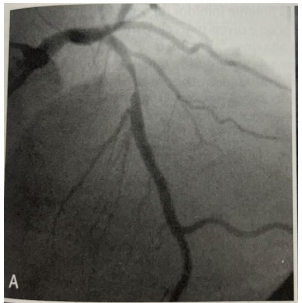

Durante a internação realizou cineangiocoronariografia:

BRAUNWALD. Tratado de Doenças Cardiovasculares. 9ª Ed. Fig. 58-10; pág.1309.

O diagnóstico e a artéria acometida são, respectivamente.